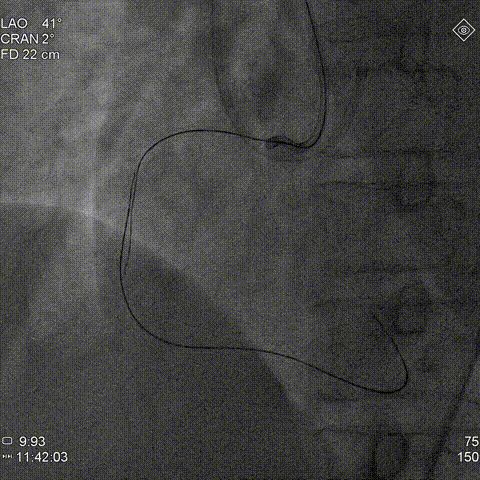

右冠造影:右冠近段完全闭塞,可见大量桥侧枝血管,结合冠脉CTA考虑闭塞段病变合并钙化,同时结合左冠血管扭曲考虑右冠1-2段转弯处存在血管成角扭曲可能;闭塞段入口并不明确,故J-CTO评分2-3分。

2、右冠闭塞段入口不明,近段血管不足以支撑血管内超声导管进入,故对于入口的多投照体位评估尤为重要,若近段入口进入困难,术中可启动BASE技术主动进入内膜下完成与逆向导丝交汇;考虑血肿控制、闭塞段钙化及提高手术效率,术中可尽早使用导引延长导管(本病例选用6F Telescope™导引延长导管)。